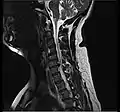

L'imagerie par résonance magnétique peut montrer la hernie, le canal vertébral, les nerfs, les tissus environnants. Les tissus mous sont les mieux analysés par cet examen qui est le plus performant pour le diagnostic de hernie discale. Les images pondérées en T2 montrent clairement la hernie.

IRM cervicale sagittale montrant une hernie discale de niveau C5-C6.